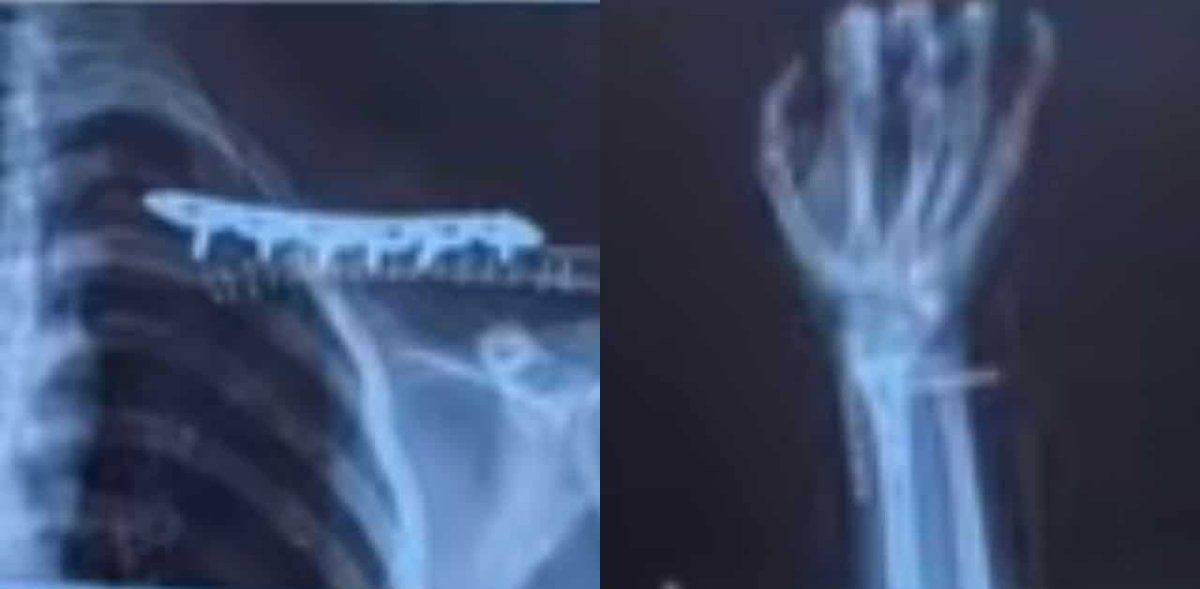

The accident occurred on 1 December, just outside the university campus. La Min Khaing reported that a Thai driver ran a red light, crashing into a motorcyclist making a U-turn. This impact caused the motorcycle to slide across the road and collide with La Min Khaing's own motorcycle. Tragically, the male motorcyclist died on the scene, while La Min Khaing suffered serious injuries, including a broken wrist and fractured clavicle.

image.jpeg